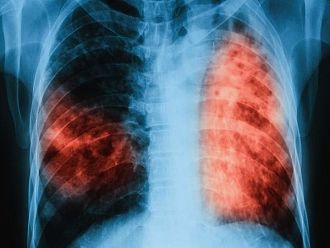

В резултат на изпълнението на Националните програми за превенция и контрол на туберкулоза в България e налице тенденция за трайно намаляване на заболяемостта от туберкулоза - от 26.6 на 100 хил. население през 2012 г. до 14.8 на 100 хил. през 2022 г. (по предварителни данни).

Общият брой на регистрираните с туберкулоза лица през 2022 г. е 775 (по предварителни данни). За сравнение през 2012 г. техният брой е 2 280. Запазва се тенденцията броят на мъжете да е два пъти по-голям от този на жените. Най-засегнати са възрастовите групи, както следва: от 45-54 г. (23%), над 65 г. (22%) от 55-64 г. (20%), от 35-44 г. (16%), от 25-34 г. (9%). През 2022 г. са регистрирани 49 случая на туберкулоза във възрастовата група от 0-17 г., което е 6.3% от всички случаи в страната.

Туберкулозата е лечима и предотвратима, стига да бъде открита навреме и да бъде проведено качествено лечение.